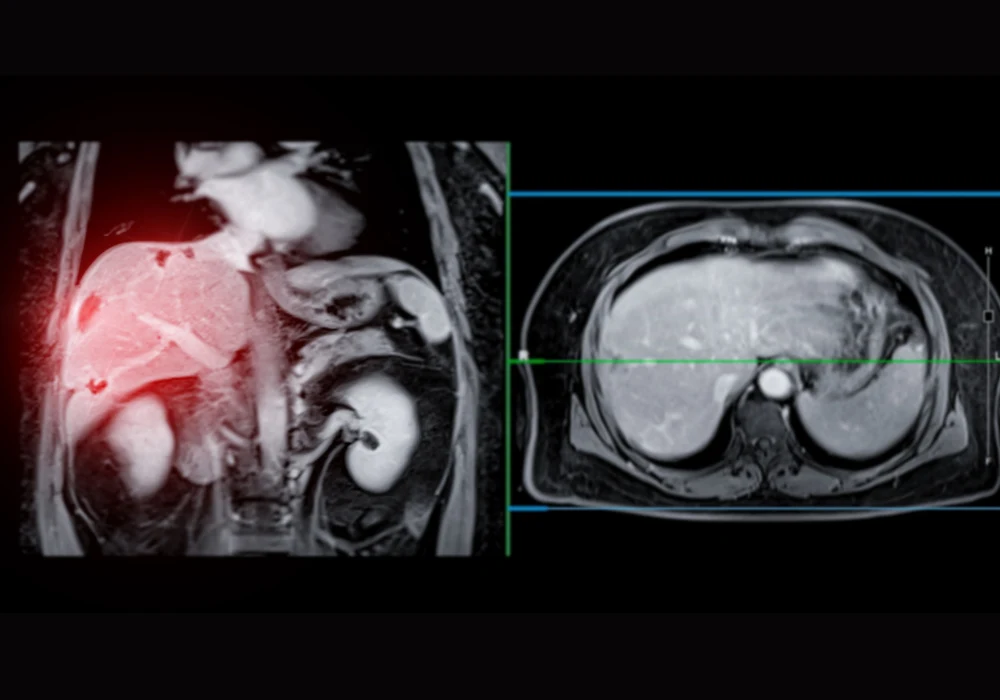

Magnetic resonance imaging (MRI) plays a vital role in the detection and characterisation of liver lesions, particularly through T1-weighted imaging during various contrast-enhanced phases. While these techniques offer rich diagnostic data without ionising radiation, they face practical limitations, notably the requirement for prolonged breath-holds. These limitations can impair image quality due to motion artefacts and reduce diagnostic confidence.

Recent advances in artificial intelligence have led to the development of reconstruction techniques that may improve image quality and shorten scan duration. A study published in European Radiology Experimental evaluated the efficacy of an AI-augmented T1-weighted hepatobiliary-phase liver MRI sequence in comparison to standard imaging methods, with a focus on image quality and lesion detectability.

The study involved fifty patients undergoing gadoxetate-enhanced liver MRI, who were imaged using both standard and AI-augmented T1-weighted sequences. Two sequences were used: a routine 17-second breath-hold and an accelerated 12-second breath-hold with reduced phase resolution. Each was reconstructed using standard methods, neural network (NN)-only, iterative denoising (ID)-only and a combined NN+ID approach.

Quantitative analysis revealed that the 17-second NN+ID images had a significantly higher liver-to-portal vein contrast-to-noise ratio (CNR) compared to both the standard and NN-only reconstructions. Qualitatively, both the 17- and 12-second NN+ID images scored higher than the standard reconstruction for overall image quality, CNR and edge sharpness of vessels and lesions. These results underscore the potential of AI-augmented reconstruction to enhance visual clarity, reduce artefacts and improve diagnostic confidence without extending scan time.

Shorter breath-hold durations are particularly beneficial for patients with limited respiratory capacity. The study showed that reducing the acquisition time from 17 to 12 seconds using the NN+ID approach did not compromise image quality. Both versions performed similarly across all measured parameters, including sharpness, CNR and susceptibility to respiratory motion artefacts. While one of the two readers observed fewer motion artefacts in the NN+ID series, the discrepancy in assessment between the two readers was attributed to individual interpretation and experience.

Importantly, lesion detection rates were comparable between the 12-second NN+ID and the 17-second standard reconstructions. There was no significant difference in the number of lesions identified or the size of the smallest detectable lesion. These findings suggest that AI augmentation not only preserves diagnostic integrity but also allows more efficient and patient-friendly imaging, potentially leading to wider clinical adoption.